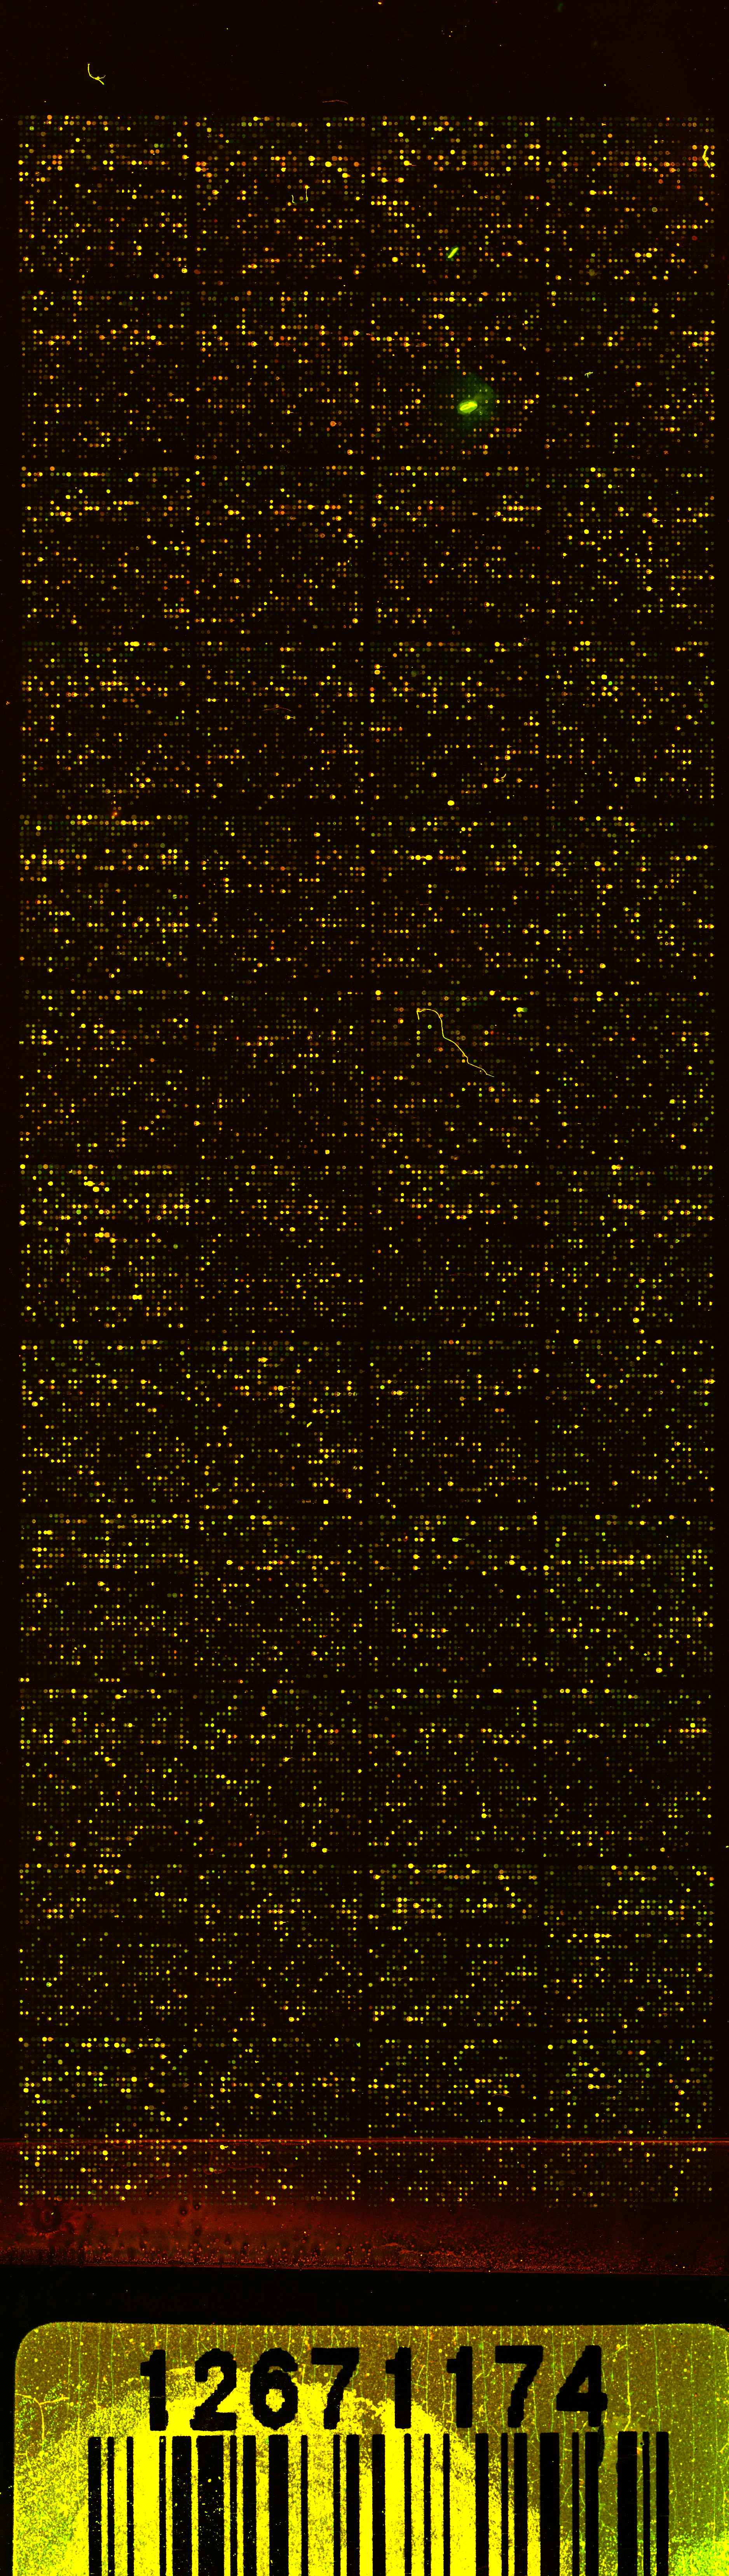

Expression profiles of differentially regulated genes at three time points (12, 24 and 72 hours) between UUO and UN. Green colour represents suppressed genes/sequences compared to control and red colour abundantly expressed features over control. The unsupervised hierarchical cluster algorithm groups kidneys according to the similarity in their molecular signature next to each other (#1 to 3). UN kidneys from the same time point as well as UUO kidneys from the same time group nicely together. Shaded areas in the heat map represent other time points as the time indicated on the left.

Expression profiles of more than twofold differentially regulated genes between UUO and UN. Green colour represents suppressed genes/sequences compared to control and red colour abundantly expressed features over control.